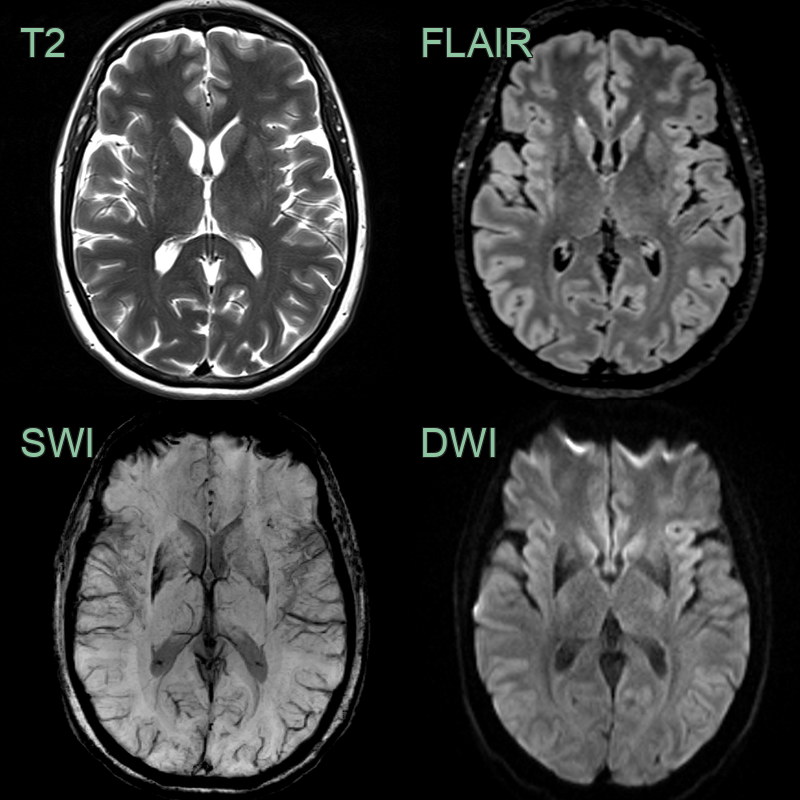

- MRI findings:

- Putaminal atrophy with T2 hypointensity

- "Hot cross bun" sign in pons (T2/FLAIR hyperintensity)

- Cerebellar atrophy

- "Putaminal rim" sign (T2 hyperintensity at lateral putaminal border)

- 80-year-old patient presented with asymmetric parkinsonism (left > right) with freezing and early falls with poor response to levodopa.

- MRI showed putaminal atrophy, susceptibility artefact and T2-hyperintensity along the lateral aspect of the putamina.